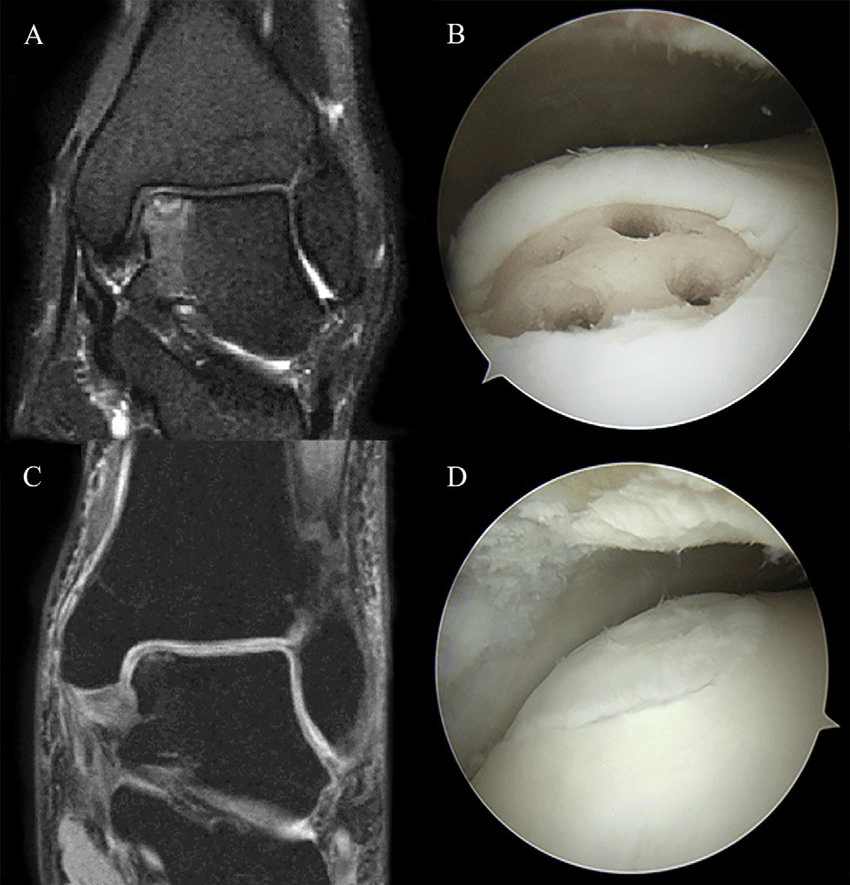

Dacă fragmentul osos afectat devine pațtial sau total desprins, este necesară intervenția chirurgicală pentru îndepărtarea corpului liber. După îndepărtare se practică foraje în locul care a fost ocupat de fragmentul îndepartat, cu scopul stimulării formării de noi vase de sange și de țesut fibros (Figura 1).

În unele cazuri, chirurgul ortoped poate efectua operația sub control artroscopic. Dacă este folosit artroscopul, interventia necesită incizii mai mici decat operația deschisă. De asemenea, timpul de recuperare și reintegrare este scurtat.